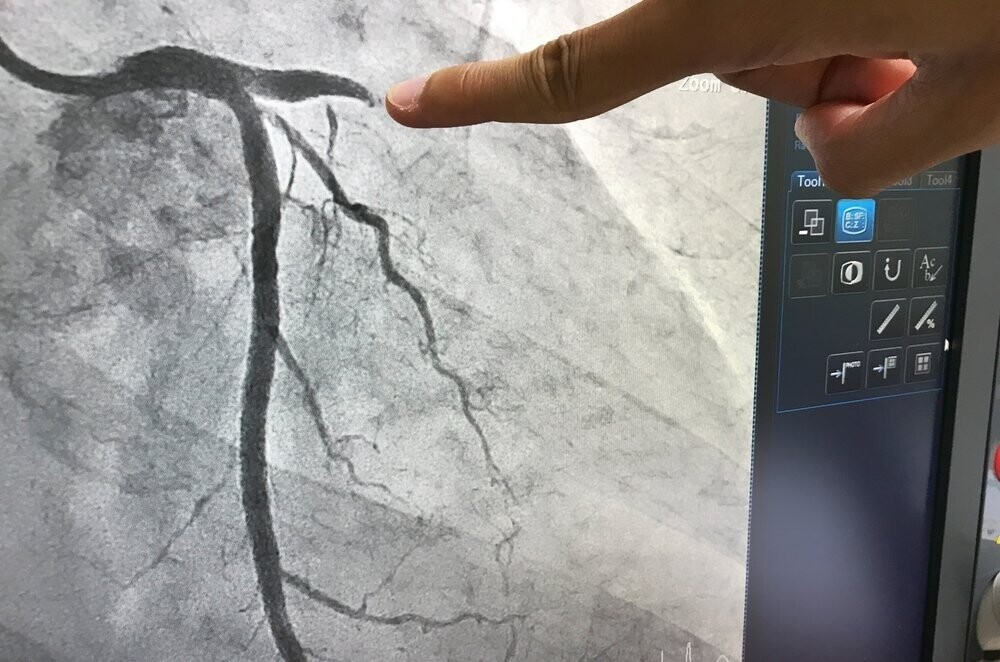

- В это время оборудование выполняет рентген-съемку и видеозапись процесса наполнения кровеносных сосудов контрастным веществом.

- После завершения съемки, когда необходимые для изучения снимки сделаны, катетер извлекают, а на место прокола накладывают давящую повязку.